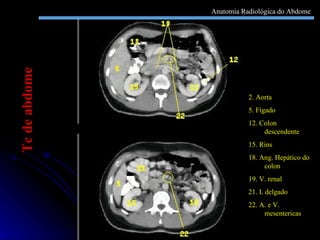

2. Aorta 5. Fígado 12. Colon descendente 15. Rins 18. Ang. Hepático do colon 19. V. renal 21. I. delgado 22. A. e V. mesentericas Tc de abdome Anatomia Radiológica do Abdome

2. Aorta 5.Fígado 12. Colon descendente 15. Rins 18. Ang. Hepático do colon 19. V. renal 21. I. delgado 22. A. e V. mesentericas Tc de abdome Anatomia Radiológica do Abdome